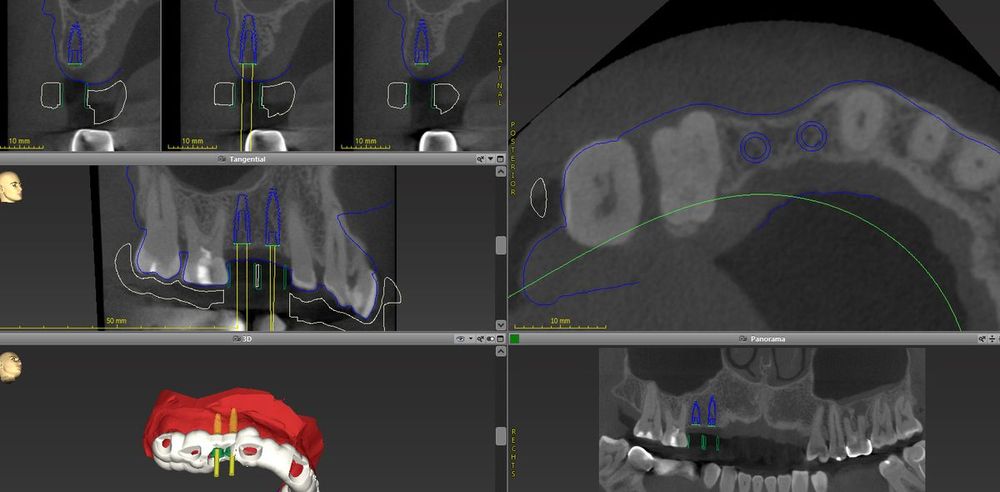

Mittels 3D-Röntgen (DVT - Morita X800) und digitaler Rekonstruktion (CoDiagnostiX) bestimmen wir vorab die optimale Position der Implantate virtuell am Computer. Diese Position wird später passgenau mit Hilfe einer Navigationsschablone in den Mund übertragen. So erhöhen wir die Sicherheit der Implantation für Sie auf ein Höchstmaß. Des Weiteren verkürzt diese Vorgehensweise die Zeit des Eingriffs, verringert die Wundfläche und begünstigt die Heilung. Genügt das Knochenangebot für eine Implantation einmal nicht, dann kann dieses mittels Knochenaufbau ggf. durch Unterstützung unserer Kollegen in der Kieferchirurgie verbessert werden.